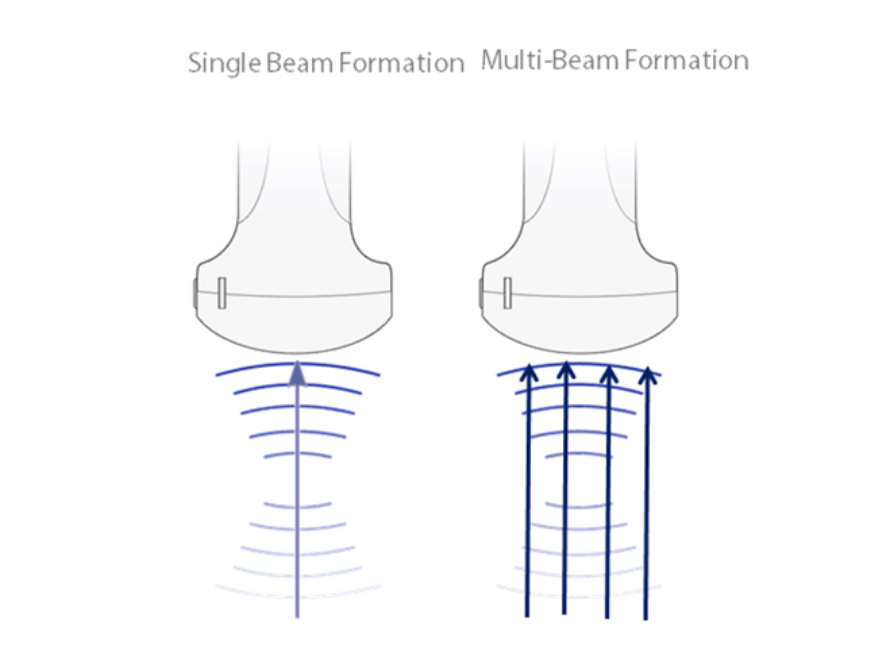

Multi-Beam Formation

Maximum 4 times tasking for one transmitted beam, resulting in excellent time resolution and higher frame rate.